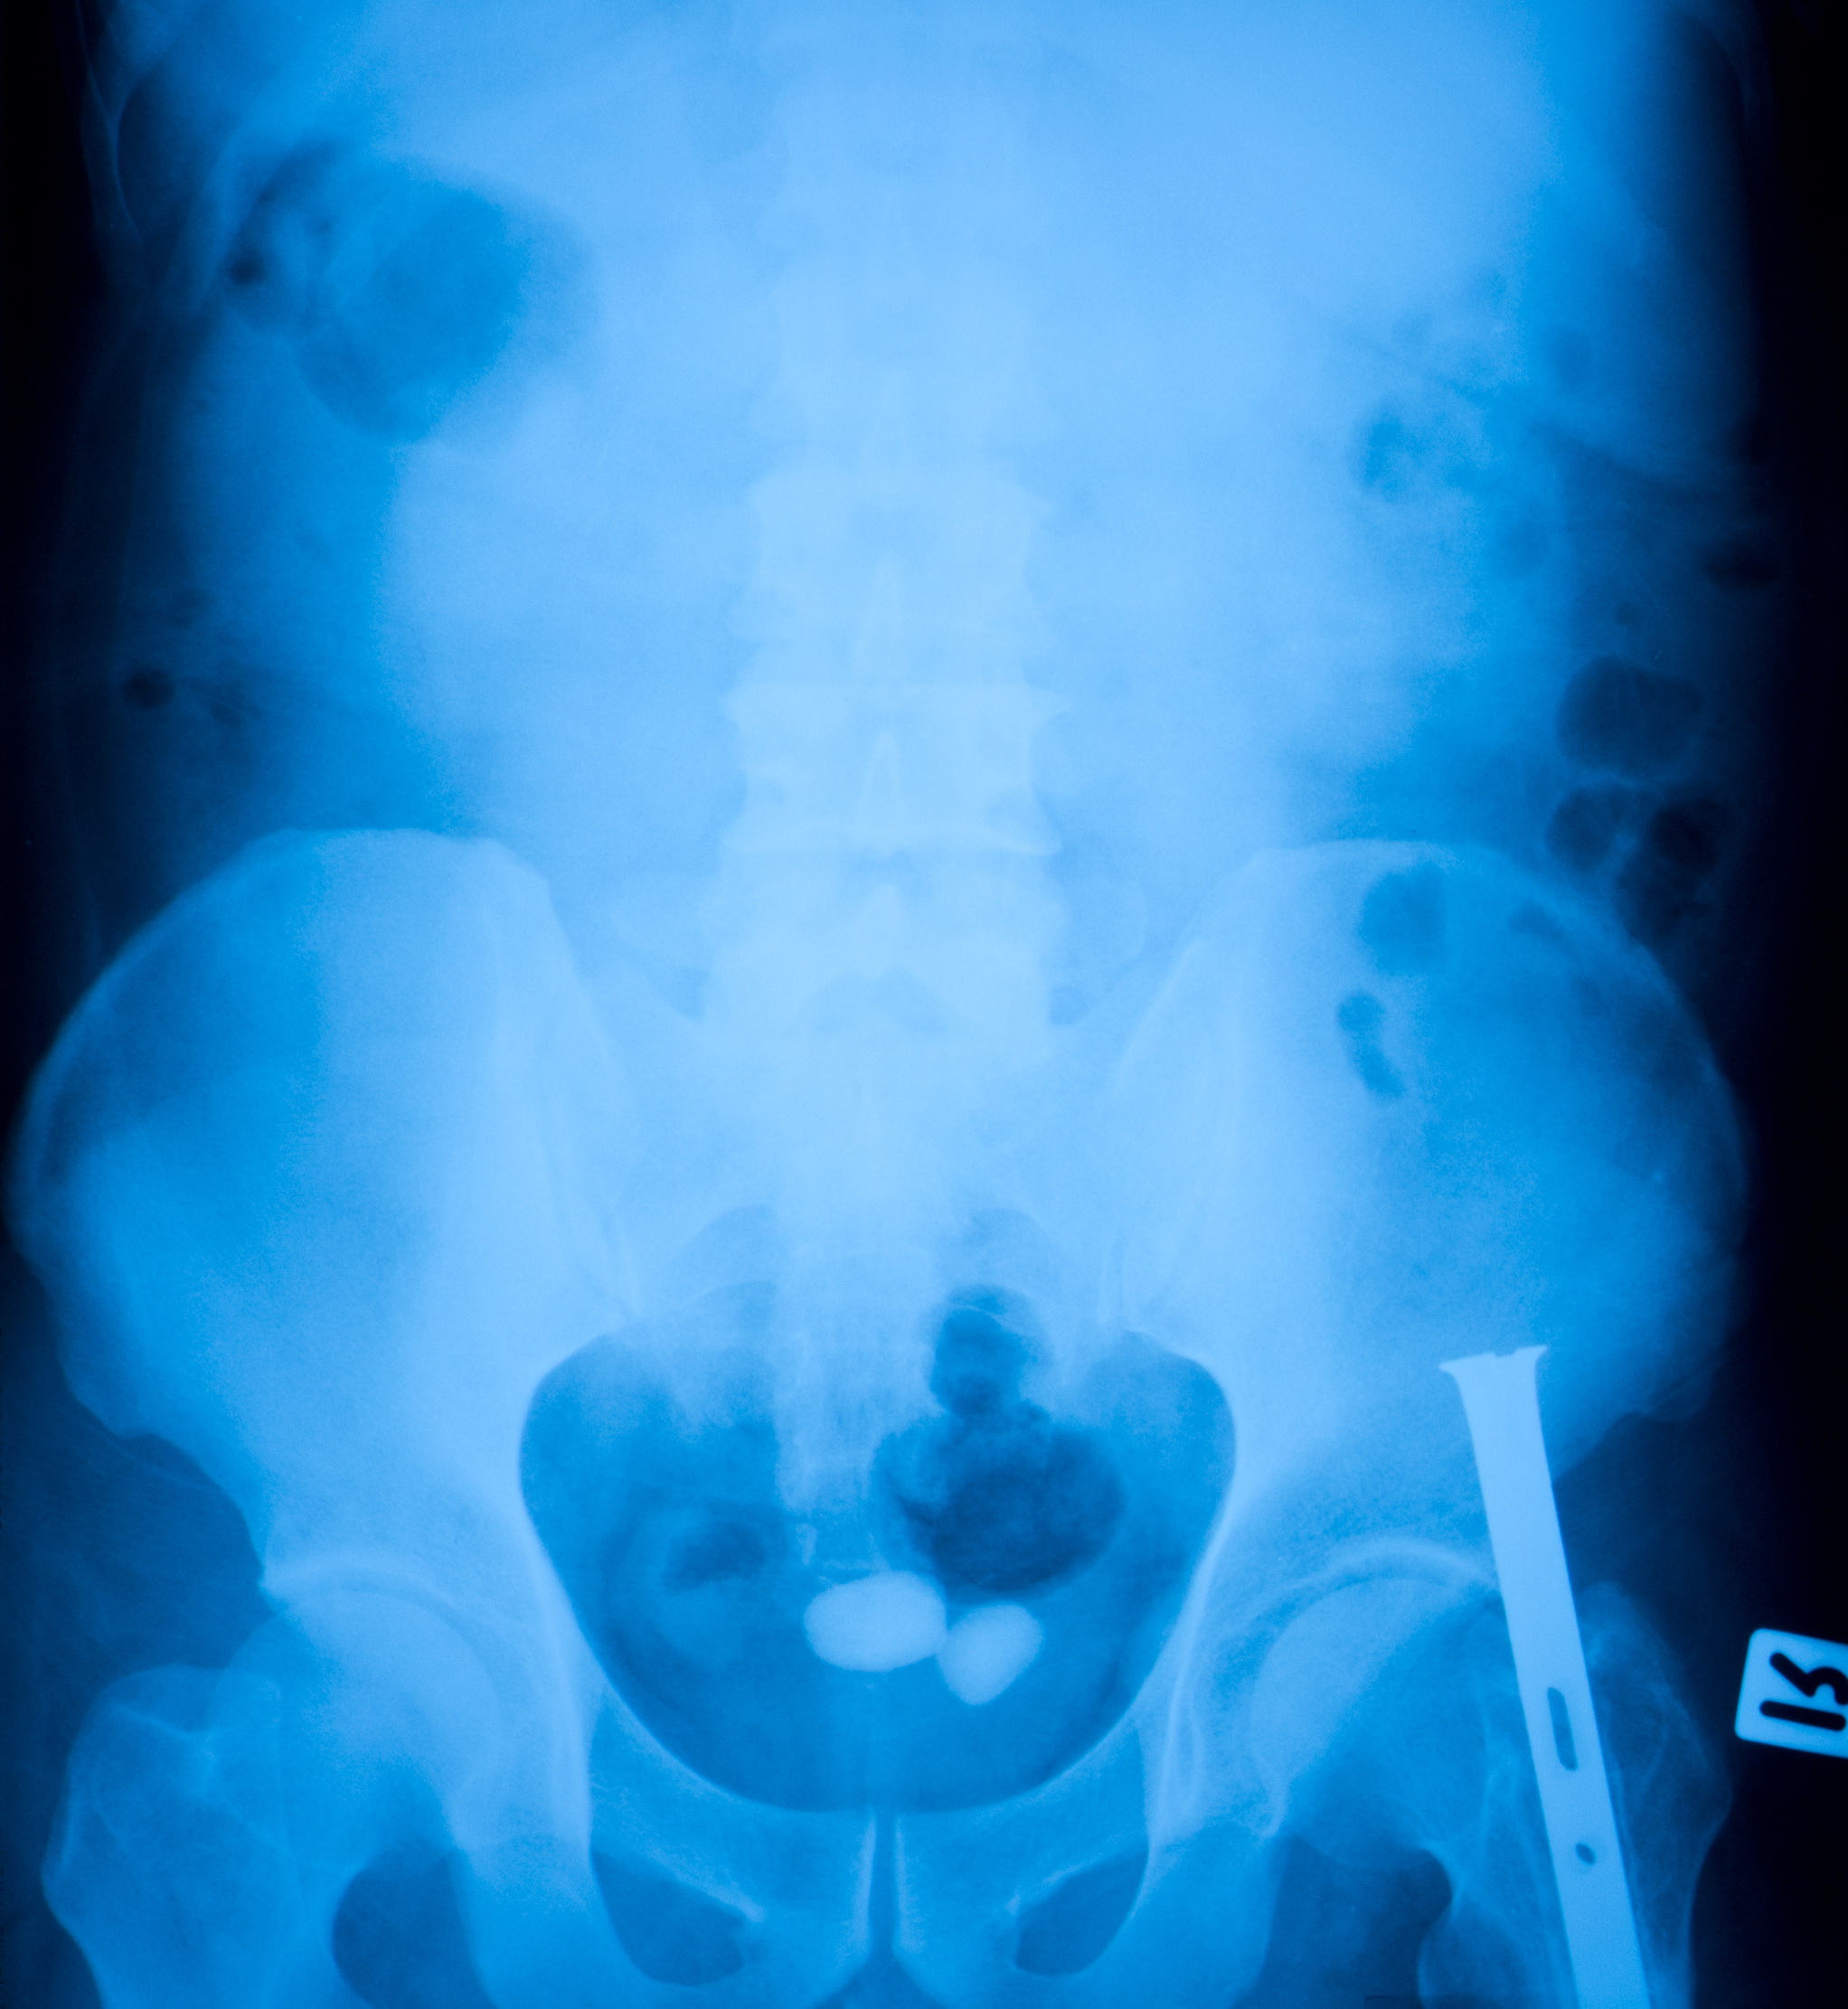

요로결석은 비뇨기관에서 소변의 성분들이 결정으로 변하여 돌이 형성되는 질병입니다.

요로결석은 소변이 만들어져 배출되는 길인 요로에 결석이 생기는 질환입니다. 결석은 주로 칼슘, 수산염, 인산염 등의 무기질이 소변에 녹지 못하고 결정으로 뭉쳐져 생성됩니다.

요로결석은 신장, 요관, 방광, 요도 등 어디에서나 생길 수 있지만, 가장 흔하게는 요관에서 생깁니다. 요관은 신장에서 방광으로 소변을 운반하는 관으로, 지름이 약 5mm 정도입니다. 결석이 요관에 생기면 통증, 구역질, 구토, 혈뇨 등의 증상이 나타날 수 있습니다.